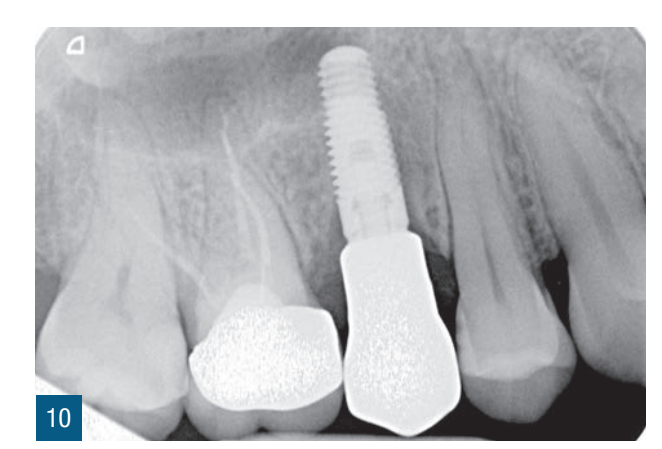

Пацієнтка 36 років звернулася до нас з частковим переломом коронки другого премоляра праворуч (1.5). Після перевірки неможливості консервативного відновлення було заплановано імплантно-протезне лікування з негайною екстракцією для заміни ураженого елемента (Рис. 1,2). Пацієнтка, не курець, була класифікована як ASA 1. Було виконано локалізовану CBCT в ураженій області для перевірки наявності та морфології вестибулярної кісткової стінки навколо елемента, що підлягає екстракції, в альвеолярному відростку. Перед екстракцією 1.5 була виконана цифрова внутрішньоротова відбитка (iTero Flex, Align Technology) зуба та прилеглих ділянок (Рис. 3). Після плескальної анестезії була виконана екстракція, обмежуючи травму пародонтальних тканин, розділяючи корені та використовуючи міні-важелі та синдесмотоми для збереження вестибулярної кісткової пластини. Оцінюючи цілісність альвеоли та сприятливі анатомічні умови, переходять до встановлення імплантату розмірів, що забезпечують адекватну первинну стабільність (4.1 x 11,5 TSVH ZimmerBiomet). Імплантат розміщується в близькій до піднебіння позиції відповідно до вказівок літератури (Рис. 6,7), заповнюючи проміжок між імплантатом та вестибулярною кістковою кортикою за допомогою гетерологічної кісткової пересадки (Copioss Zimmer-Biomet). Монтажний пристрій формують так, ніби це абатмент, і після його закручування на імплантаті проводять сканування. З цифрового внутрішньоротового сканування виконується CAD проектування гвинта загоєння (Рис. 4). У проекті буде використано як передекстраційне сканування, так і сканування з монтажним пристроєм, перетвореним в абатмент, щоб максимально точно відтворити гвинт загоєння. Морфологія гвинта загоєння відтворить існуючі тканинні умови на момент хірургії та дозволить уникнути естетичних дефектів у рожевій естетиці. Завершивши цифрове проектування, виконується 3D-друк з смоли (Lab2 Formlab) кастомізованого гвинта загоєння. Після завершення друку, отриманий гвинт загоєння з смоли Nextdent цементується з авто- та фото-твердим смолистим цементом (Relix Unicem, 3M) до абатмента, отриманого з монтажного пристрою, а потім закручується на імплантат (Рис. 5,6). Було проведено рентгенологічні контролі через три місяці та через рік (Рис. 7,8). Через 3 місяці була виготовлена остаточна коронка через цифровий потік з тим самим сканером та спеціальними сканбоді (Gentek, Zfx), які дозволяють ідентифікувати точне просторове положення імплантату. Через тиждень була передана остаточна монолітна коронка з фарбованої цирконії, закручена на ti-base (Рис. 9,10). Через рік було виконано ще одне сканування для оцінки з часом можливих об'ємних змін періімплантних тканин. Сканування, виконані на етапі передекстракції та через рік, були оброблені за допомогою спеціалізованого програмного забезпечення (meshlab) для оцінки розмірних змін (Рис.11-13).